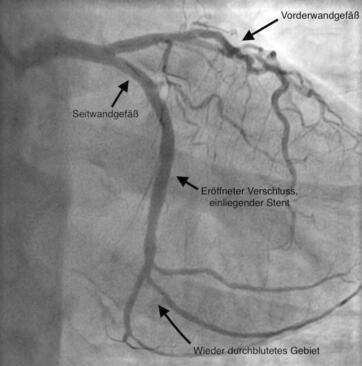

Bei der Linksherzkatheteruntersuchung werden neben der Darstellung der linken Herzkammer (Ventrikulographie) die Herzkranzgefäße mittels Röntgenkontrastmittels (Koronarangiographie) sichtbar gemacht. Die Linksherzkatheteruntersuchung wird in der Regel durch Punktion des rechten/linken Leistengefäßes durchgeführt, kann aber auch durch Punktion des Gefäßes am Handgelenk bzw. an der Ellenbeuge vorgenommen werden. Mit der Linksherzkatheteruntersuchung können Einengungen bzw. Verschlüsse des Herzkranzgefäßes, die Pumpfunktion der linken Herzkammer und der Schweregrad der Herzklappenfehler (Undichtigkeit/Einengung) beurteilt werden.

Die Koronarangiographie (Darstellung des Herzkranzgefäßes mittels Röntgenkontrastmittels) führt zum Nachweis von Einengungen, Verkalkungen und Verschlüssen der Herzkranzgefäße. Sie ist eine wichtige Voraussetzung, um zu entscheiden, ob eine medikamentöse Therapie, eine Ballonaufdehnung (PTCA) oder eine Bypassoperation sinnvoll ist. Im Falle einer Einengung des Herzkranzgefäßes kann diese in der gleichen Sitzung mit Ballonaufdehnung (PTCA/PCI) und Stent (Gefäßstütze) behandelt werden.

Die früher verwendeten konventionellen Metallstents bilden heutzutage eine große Ausnahme und werden nur in speziellen Fällen implantiert. Die überwiegende Mehrheit aller Stents sind medikamentenbeschichtete Stents, die eine überschießende Proliferation von Zellen, welche zu einer Wiederverengung des Gefäßes führen würden, hemmt.